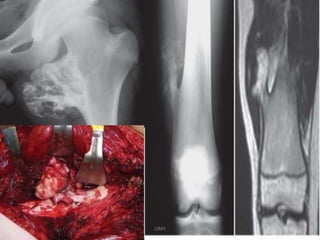

ANJALI ,20F,ABC

Rx-Curettage+ G Bone grafting

PRE OP IMMEDIATE POST OP FOLLOW UP

UMY

DHRUV 8/M ABC

Rx-curettage+ Chron os grafting